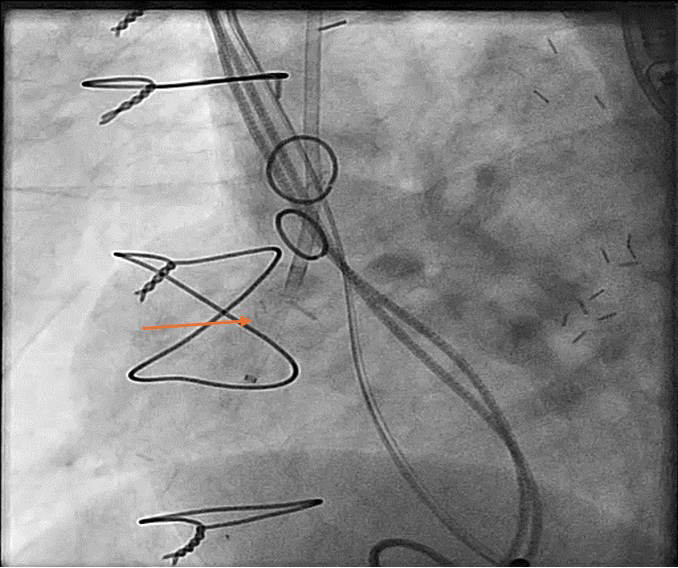

Figure 4

Figure 4. Angiogram using pigtail wire confirming the placement of plug and blocking of blood flow.